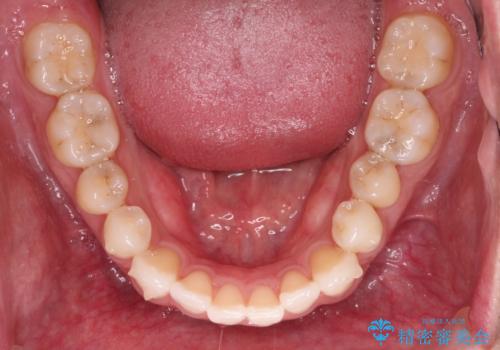

- 上下前歯の叢生を気にして来院された患者様です。

費用を抑え、期間もあまりかけずに治療をしたいとのことで、インビザライン・ライトを用いて矯正治療を行うこととしました。